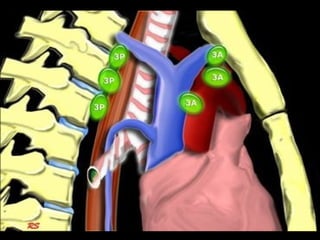

3. Prevascular & prevertebral LNs

• Prevascular LNs (3A) are located anterior

to the vessels.

• Prevertebral (retrotracheal) LNs (3B) are

located anterior to the spine.

• Prevertebral LNs are not accessible

through mediastnioscopy but only

available through Endoscopic U/S.